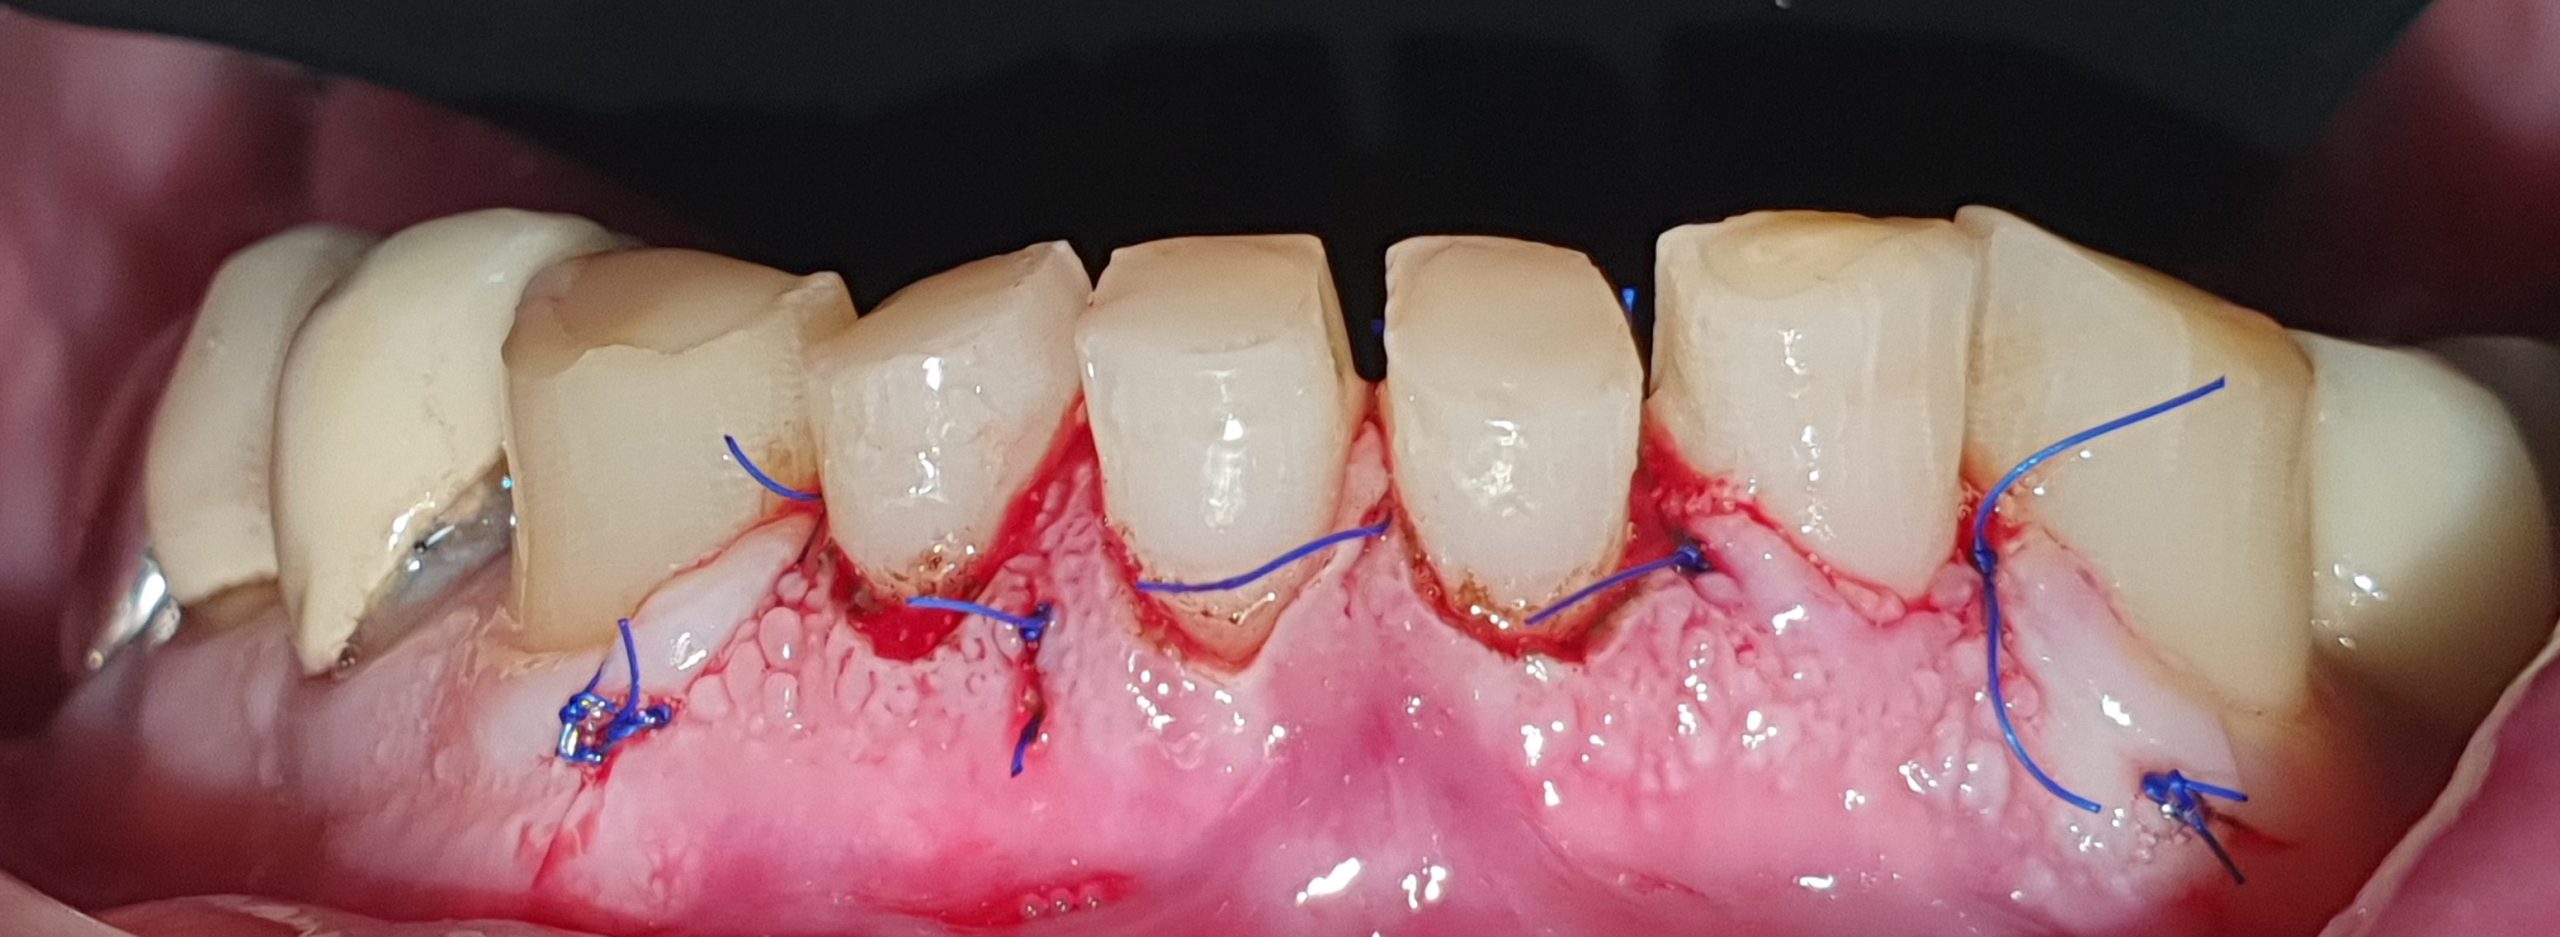

- The second stage: do the crown lengthening procedure for the lower front teeth

The second stage: do the crown lengthening procedure for the lower front teeth

The third stage: do porcelain veneer for the lower front teeth

The lower front teeth after porcelain veneer procedure